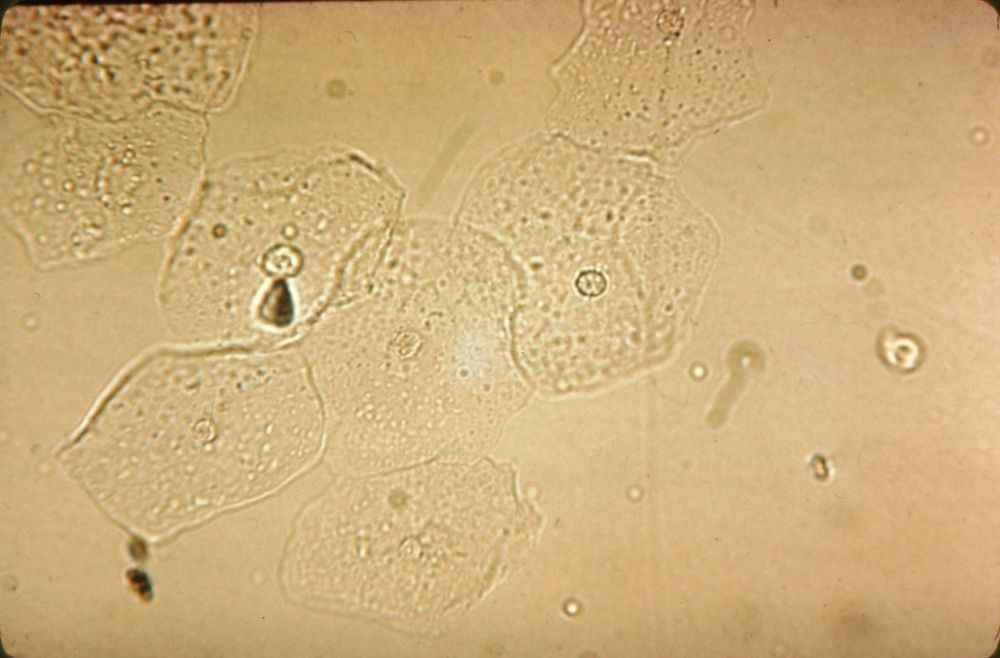

Image:

Caudate Cell (image/jpeg)

Caudate Cells |